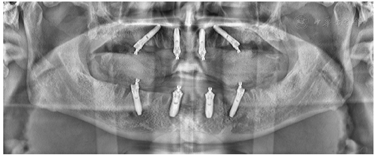

17、25、26、27、28、31、34、37、38、45、47、48缺失,缺牙区牙槽嵴低平。25、34、37拔牙创处于愈合期。口腔卫生情况欠佳,探诊深度PD 4-11mm,附着丧失1~10 mm,牙龈暗红,质地疏松,探诊出血,BOP%=100%,可探及连续龈下结石。18、16、11、21、32、33、35、36、41、42、43、44、46松动III度,15、14、13、12、22、23、24松动II度。前牙深覆牙合,右侧后牙咬合中性关系(图1)。颞下颌关节检查未见异常。影像学检查:初诊全景片显示余留牙牙槽骨水平性吸收至根尖1/3(图2)。术前CBCT截图显示15、14、13、12、22、23、24牙槽骨吸收至根中1/3水平,其余牙牙槽骨吸收至根尖1/3不等(图3)。

治疗过程(1)手术方案设计:拔除余留牙后,上颌拟在12、22植入2颗轴向植体,15、25植入2颗倾斜植体,下颌于32、42植入2颗轴向植体,35、45区域植入2颗倾斜植体,种植体倾斜角度小于45°,术后制作临时种植固定义齿,6月后戴终义齿(钛支架加丙烯酸树脂材料)。(2)种植一期术前测量垂直距离。术中拔除上下颌余留牙,分别于16-26、36-46区牙槽嵴顶近远中向切开牙龈黏膜,翻瓣,搔刮拔牙窝内炎性肉芽组织,平整牙槽嵴顶骨嵴,分别于12、15、22、25、32、35、42、45区定点,逐级备洞,12、22、32、42区轴向植入Nobel Speedy 4x13mm种植体,15、25、35、45区远中倾斜植入Nobel Speedy 4x15mm种植体。初期稳定性均达到35N·CM。15、25放置RP 5 mm 30°复合基台,12、22放置RP 3 mm 17°复合基台。32、42放置RP 2 mm 0°复合基台,35、45放置RP 4mm 30°复合基台,放置愈合帽,修整牙龈黏膜,缝合牙龈(图4)。术后拍摄全景片(图5)(3)即刻负重制取上下颌印模,制作蜡堤记录上下颌颌位关系,采用息止颌位法确定垂直距离,吞咽咬合法确定水平关系,转移颌位关系后,手术当日制作临时固定义齿修复至第二前磨牙并戴入固定,调整咬合接触(图6)。